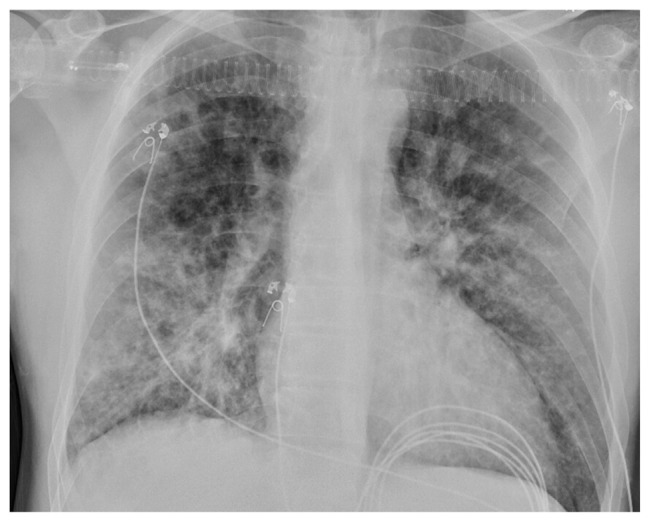

Abstract Image